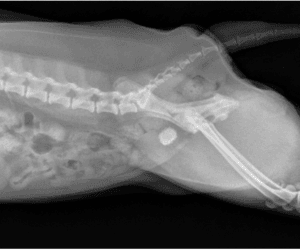

Perineal Urethrostomy

This procedure is most often performed in male cats with a history of urinary obstruction. Urinary obstruction is a common, life-threatening disorder in male cats in which they are unable to urinate. This can result in toxin build up, acute kidney injury and heart arrhythmias. In cats with bladder stones that can be flushed into the bladder, a cystotomy is performed to remove the stones. If a cat has multiple occurrences that cannot be unblocked or managed medically, the next step is a perineal urethrostomy (“PU”), or surgical widening of the urethra. This procedure is intended to provide a permanent opening that allows crystals, mucus plugs, or small stones to pass out of the urethra, thus minimizing the chance of re-obstruction.

$1750